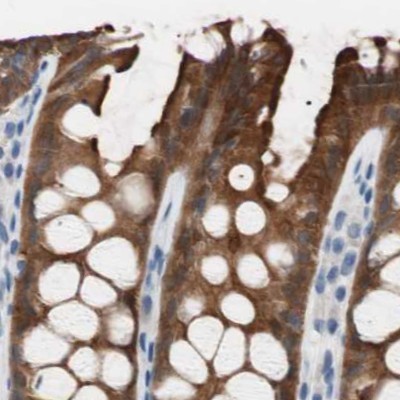

- Immunohistochemistry-Paraffin: Villin 1 Antibody [NBP1-85335] - Staining of human duodenum shows strong luminal membranous and cytoplasmic positivity in glandular cells.